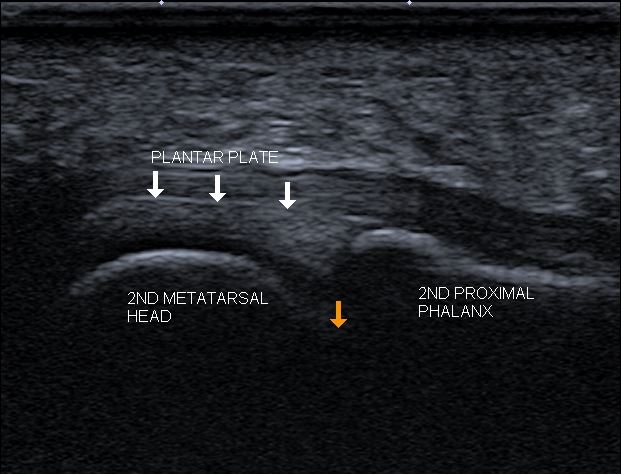

diagnostic ultrasound image of the plantar plate

Diagnostic ultrasound is performed to check the quality of the plantar plate.